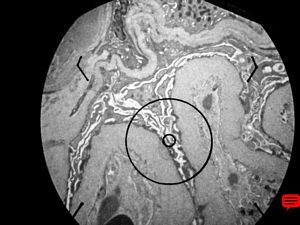

M,6y. | Alport syndrome- digital photo from the screen